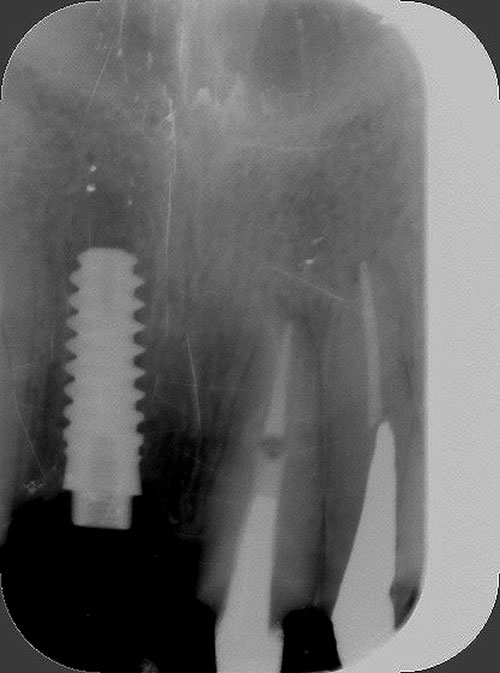

Mientras dichos movimientos ortopédicos se producen (período que supondrá otros seis meses), estudiamos los actos quirúrgicos a realizar en los cuatro implantes que pondremos. De acuerdo al estudio Desatascan realizado observamos tres situaciones diferentes: 1º-El Primer Molar Inferior Izquierdo, lo instalamos mediante Cirugía Minimamente Invasiva , con la aplicación de una Férula Quirúrgica Obtenida de los datos del scanner tratados con un programa de CMI (Cirugía Minimamente Invasiva), previa prueba en un modelo estereolitográfico, ya que la altura ósea era apenas de 9 mm. 2º- El Primer Molar Superior Derecho, se implantará mediante una ligera Elevación Atraumática (Trans alveolar) de Seno una vez logrado el espacio mesio distal necesario. 3º- El Incisivo Central Superior Derecho ausente, cuenta con un sustrato óseo prácticamente inexistente. El espesor de la tabla era de menos de 2 mm. Los caminos posibles a seguir para contar con una Rehabilitación de piezas independientes son dos: Optamos por esta segunda opción por ser menos cruenta y no necesitar de una zona dadora. Técnica esta que pondremos en práctica en dos etapas diferidas: 1º-Incisión horizontal palatinizada, incisiones peri rodetes gingivales e incisiones de descarga. Dilatación que comenzamos con dos incisiones de descarga sobre la cortical vestibular realizadas con disco. y el comienzo de la dilatación propiamente dicha mediante una hoja de bisturí, para luego seguir con un periostótomo . Recién después de alcanzada una cierta separación de la cortical vestibular de la palatina, empezamos con los dilatadores roscados. En este punto podríamos haber utilizado sin riesgos un Implante de 3,8 mm de diámetro, pero a fin de mejorar la estética del pilar emergente decidimos rellenar con material osteoconductor y osteoinductor (BiOss) y cubrir mediante membrana reabsorvible ( Bio Guide). 2º-Implantación seis meses después. Mientras se van cumpliendo los tiempos antes mencionados, y comprobamos reiteradamente la funcionalidad de la oclusión con los provisorios, tomamos impresiones definitivas y construimos primero el maxilar inferior, para definir en primer término la porción inferior de la Guía Anterior., y a nivel posterior Curvas y Microplanos. Para luego realizar los cuadrantes premolar- molar del superior: La espera de la regeneración ósea y sus tiempos pertinentes, más la espera de los tiempos de la implantación, nos obligaron a modificar las etapas del protocolo D.AT.O de manera de mantener la –D- mediante el sector superior de la GA. en provisorios, mientras fuimos resolviendo en forma definitiva los demás sectores. Ya pasados los meses necesarios para recrear un hueso adecuado en el área del Incisivo Superior Derecho, procedemos a resolver la implantación de dicha zona, observando que todo el esfuerzo dedicado al mismo había sido inútil, ya que la formación de hueso se produjo minimamente. Cuatro meses después tomamos impresiones del sector Antero Superior de la Guía Anterior, incluyendo el arrastre de un transfer . Seguimos modelando la encía con un nuevo juego de provisorios. Y se construye entonces el sector superior de la Guía Anterior. Se efectúa un control radiográfico a los 6 meses. Se ha intentado mostrar en esta Rehabilitación, que a pesar de las distintas circunstancias de cada paciente, siempre debemos tener en cuenta la necesidad de ejercer la DESOCLUSIÓN del caso como prioridad número uno, para luego perseguir la ALINEACIÓN TRIDIMENSIONAL de las arcadas y obtener así una OCLUSIÓN equilibrada. D.AT.O. ES EL PROTOCOLO QUE DEBEMOS SEGUIR EN TODA REHABILITACIÓN. BIBLIOGRAFÍA 1)William Mc Horris,B.S.,D.D.S. Oclusión. Con especial énfasis sobre :El rol funcional y parafuncional de los dientes anteriores. 2)Von Spee , Craff(Anatomista alemán, describió la curva de compensación de la articulación de molares y premolares).CURVA DE SPEE 1.89 3)Stuart,D.”Some aspects of the inervation teeth.”Procedings of Royal Society of Medicine.20:1675,19274)Muhleman,H. y Savdir,S”Tooth movility-its causes and significance”Journal of Periodontology ,36:153,Marzo ,Abril,1965. 4)Muhleman,H. Y Savdir,S”Toothmovility its causes and significance” Journal of Periodontology,36:153,marzo,abril,1965. 5-Oclusión y Diagnóstico en Rehabilitación Oral. 6-Anatomia Odontológica. 7-A contribution to the study of the movementes of the mandible. 8-Celenza F.W, Nadeskin J.F.,Oclusión.Situación actual. 9-D´Amico 10-Dawson P.E. 11-Huffman –Regenos. 12-Hobo S.-Takayama H.A. 13-Lucia V.O 14-Mc Horris. 15-Mc Horris. 16-Stuart C. 17-Vartan Veshnilian 18-Alvarez Cantoni H. AUTOR:Ratificación del Protocolo en Rehabilitación Bucal a pesar de las incidencias propias de cada caso clínico. A propósito de un caso.

No obstante pudimos implantar satisfactoriamente mediante un implante de 4.2 mm. de ancho y 14 mm. de largo, con una nueva R.O.G.

El implante se encontraba perfectamente según comprobaciones radiográficas y clínicas al sondeo.